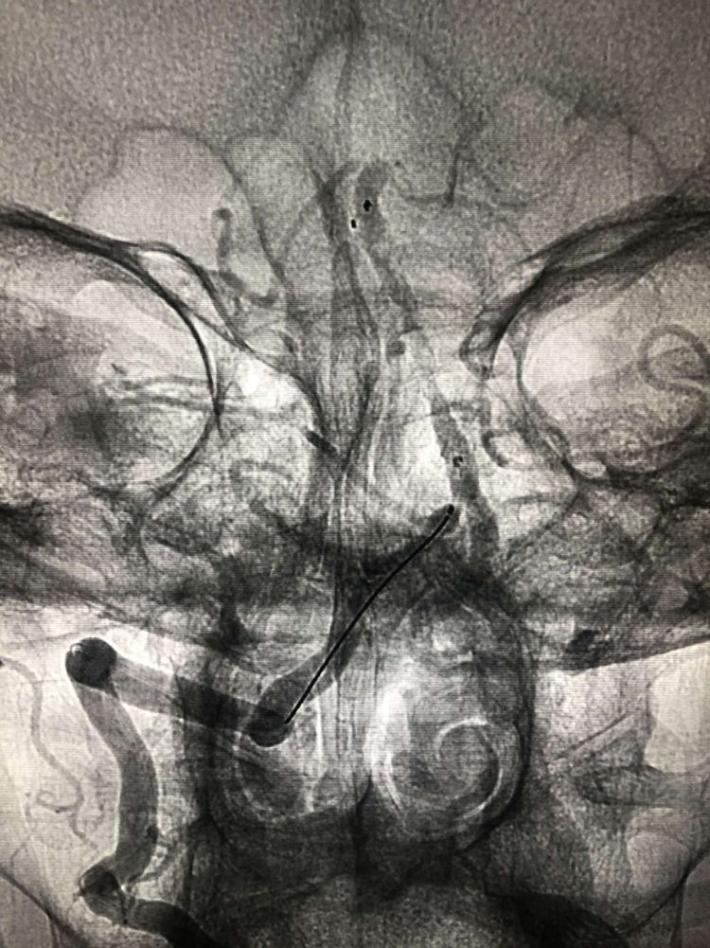

入院后75min,股动脉穿刺成功,后循环造影及右侧颈内动脉正侧位。

导丝导管通过闭塞部位,经微导管造影,证实在远端真腔内,取栓后M1重度狭窄,球囊扩张。

球囊扩张

支架植入术后前向血流通畅